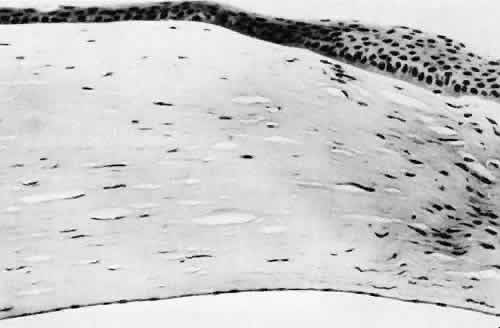

Penetrating corneal injuries involving at least one third of the stroma (Fig. 4) are covered initially by proliferating surface epithelium that may extend for a considerable distance into the stroma. The extent of corneal epithelial migration is controlled at least in part by contact inhibition of migration once contact with healthy corneal endothelial cells is established.21 Bowman's membrane has elastic properties that tend to pull the anterior margins of the wound apart. Exposure of the relatively dehydrated corneal stroma to tears and blood will cause swelling of the corneal stroma. This swelling of the stroma tends to close the wound. As the stroma heals, new collagen is produced by keratocytes or transformed monocytes. Epithelial cells will regress toward the surface. The repair collagen is different from the native collagen in size and in orientation. The healed wound is densely opaque and obvious clinically, but it may be detected histologically only by the break in Bowman's membrane.

Fig. 5. Collagen lamellae retract when cut, causing the wound to gape when incised. If the extent of the incision is limited, as in clear cornea cataract incisions, the gaping may be countered by swelling of corneal stroma exposed to aqueous media. (Hematoxylin-eosin stain; × 100.)